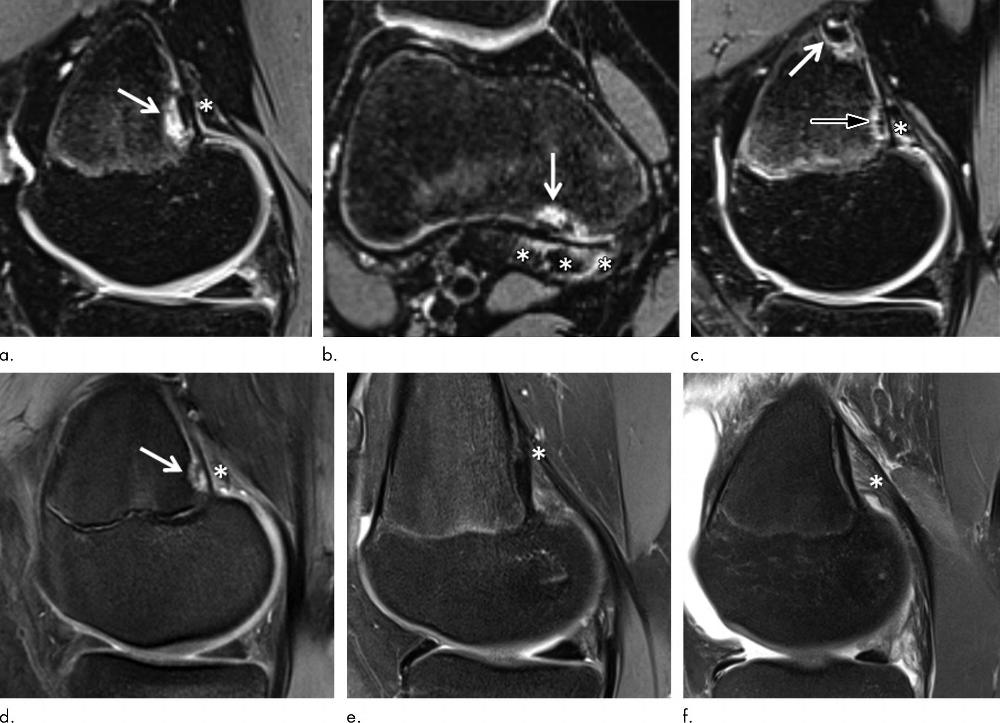

Figure 4. Images show examples of (a–d) distal femoral cortical irregularity (DFCI) at the tendon attachment of the medial head of the gastrocnemius muscle (MHG) and (e, f) knees without DFCI. (a, b) Sagittal (a) and axial (b) fat-suppressed T2-weighted MRI scans in 14-year-old female competitive skier show a 5-mm DFCI (arrow) at the distal MHG attachment (*). (c) Sagittal fat-suppressed T2-weighted MRI scan in another 14-year-old female competitive skier shows simultaneous DFCIs at the proximal (8 mm; white arrow) and distal (4 mm; black arrow) part of the MHG tendon attachment (*). (d) Sagittal fat-suppressed proton density–weighted MRI scan in 14-year-old female control participant shows a 4-mm DFCI (arrow) at the distal MHG attachment (*). (e, f) Sagittal fat-suppressed proton density–weighted MRI scans in 15-year-old female control participant (e) and 15-year-old male control participant (f) without a DFCI for comparison. The broad and fan-shaped appearance of the proximal MHG tendon (*) is especially well visualized in f because of edematous demarcation after knee trauma.